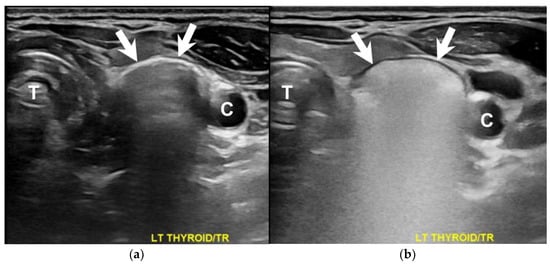

How Soda Ingestion Facilitates the Distinction between a Killian–Jamieson Diverticulum and a Malignant Thyroid Nodule